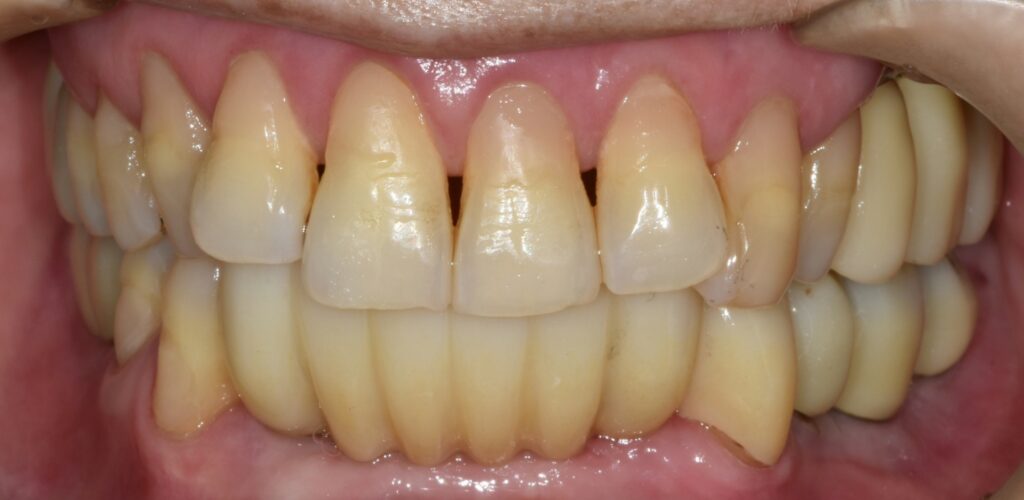

초진 상태

처음 오셨을 때의 구강 내 상태입니다.

대부분의 어금니가 심하게 흔들리고, 잇몸에서는 고름이 나오는 부위도 관찰됩니다.

어금니는 씹는 힘을 담당하는 중요한 치아이기 때문에 어금니가 무너지면 위아래 치아가 서로 안정적으로 맞물리는 교합관계도 함께 무너지게 됩니다.